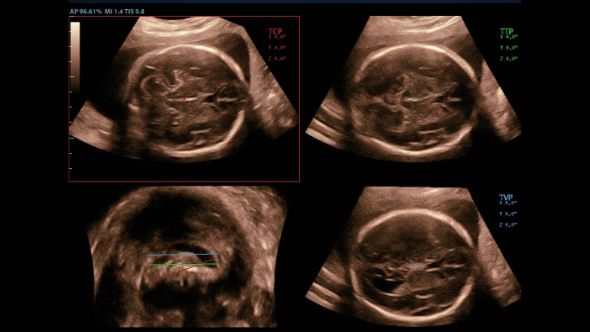

–Γ–Ω–Β―Ü–Η–Α–Μ–Η–Ζ–Η―Ä–Ψ–≤–Α–Ϋ–Ϋ―΄–Ι –Η–Ϋ―²–Β―Ä–≤–Β–Ϋ―Ü–Η–Ψ–Ϋ–Ϋ―΄–Ι –¥–Α―²―΅–Η–Κ

–Γ–Ω–Β―Ü–Η–Α–Μ―¨–Ϋ–Ψ ―¹–Κ–Ψ–Ϋ―¹―²―Ä―É–Η―Ä–Ψ–≤–Α–Ϋ–Ϋ―΄–Ι –¥–Α―²―΅–Η–Κ –¥–Μ―è –Ω―Ä–Ψ–≤–Β–¥–Β–Ϋ–Η―è –Η–Ϋ–≤–Α–Ζ–Η–≤–Ϋ―΄―Ö –Ω―Ä–Ψ―Ü–Β–¥―É―Ä –Η –Η―¹―¹–Μ–Β–¥–Ψ–≤–Α–Ϋ–Η–Ι –≤ 2D ―¹ –Φ–Η–Ϋ–Η–Φ–Α–Μ―¨–Ϋ–Ψ–Ι ―¹–Μ–Β–Ω–Ψ–Ι –Ζ–Ψ–Ϋ–Ψ–Ι, –Α ―²–Α–Κ–Ε–Β –Κ–Ψ–Ϋ―²―Ä–Α―¹―²-―É―¹–Η–Μ–Β–Ϋ–Ϋ―΄―Ö –Η―¹―¹–Μ–Β–¥–Ψ–≤–Α–Ϋ–Η–Ι;

–ï–≥–Ψ –Κ–Ψ―Ä–Ω―É―¹ ―É–¥–Ψ–±–Ϋ–Ψ ―Ä–Α–Ζ–Φ–Β―â–Α–Β―²―¹―è –≤ ―Ä―É–Κ–Β –Η –Ω–Ψ–¥–¥–Β―Ä–Ε–Η–≤–Α–Β―² –Ω―Ä–Η–Φ–Β–Ϋ–Β–Ϋ–Η–Β ―¹–Ω–Β―Ü–Η–Α–Μ–Η–Ζ–Η―Ä–Ψ–≤–Α–Ϋ–Ϋ–Ψ–Ι –±–Η–Ψ–Ω―¹–Η–Ι–Ϋ–Ψ–Ι –Ϋ–Α―¹–Α–¥–Κ–Η ―¹ –Ω–Ψ–Κ―Ä―΄―²–Η–Β–Φ –Η–Ζ –Ϋ–Α–Ϋ–Ψ–Φ–Α―²–Β―Ä–Η–Α–Μ–Α –¥–Μ―è –Μ–Β–≥–Κ–Ψ–Ι –¥–Β–Ζ–Η–Ϋ―³–Β–Κ―Ü–Η–Η.